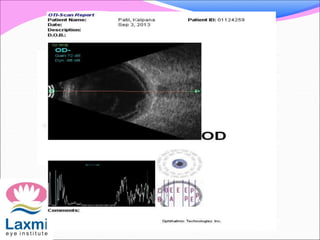

๏‚— Bscan shows vitreous echoes

Ocular ultrasonography- subretinal cyst